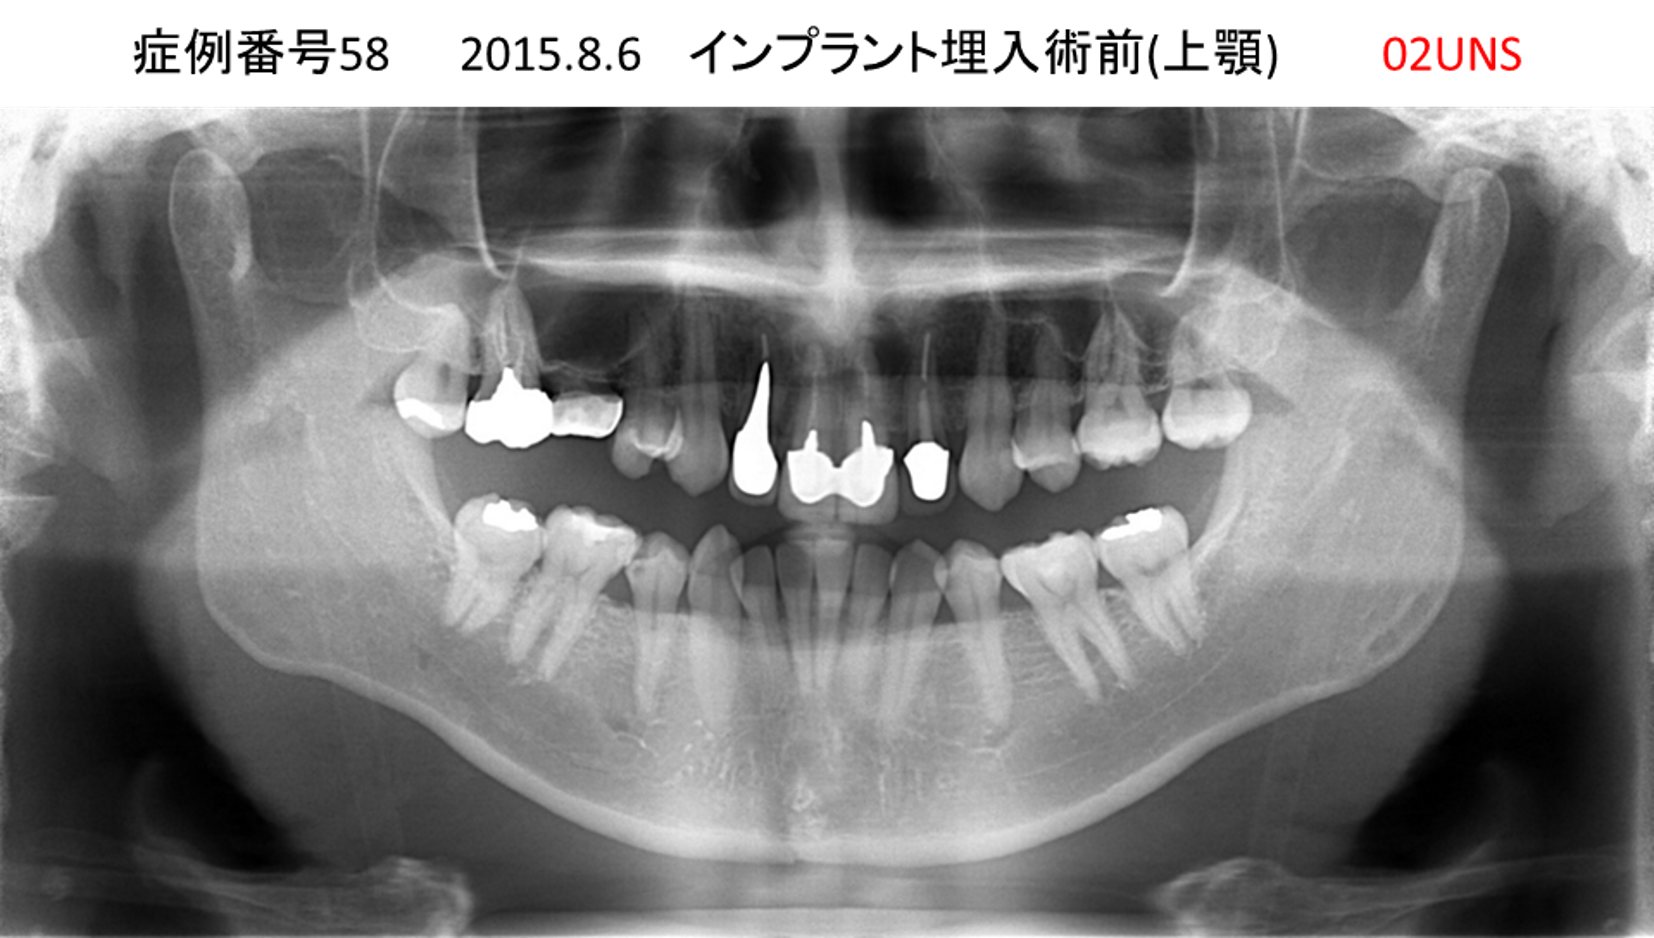

上の前歯が揺れてきてかめない患者様のインプラント症例

| 治療名称 |

インプラント |

| 治療費用 |

440万円+税 |

| 治療期間 |

6か月 |

| 患者さんの症状(主訴) |

上の前歯が揺れてきた。かめない |

| 治療内容 |

サイナスリフト、GBR、インプラント、即時荷重 |

| 治療結果 |

上の前歯の揺れが収まった。奥歯でしっかり噛める。 |

| 治療の注意点(リスク/副作用) |

インプラントが壊れたら再治療が必要 |